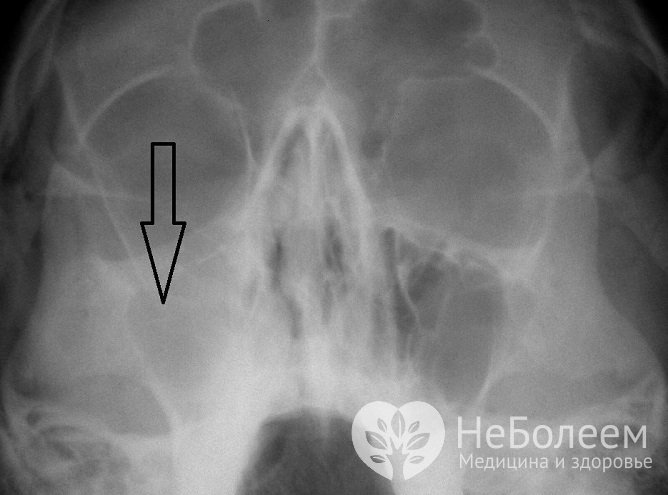

Для диагностики заболевания может быть назначена рентгенографияПри проведении рентгенограммы выявляется затемнение гайморовой пазухи. Если информативности этих методов исследования для определения, заразен или нет пациент, недостаточно, проводят пункцию гайморовой пазухи.